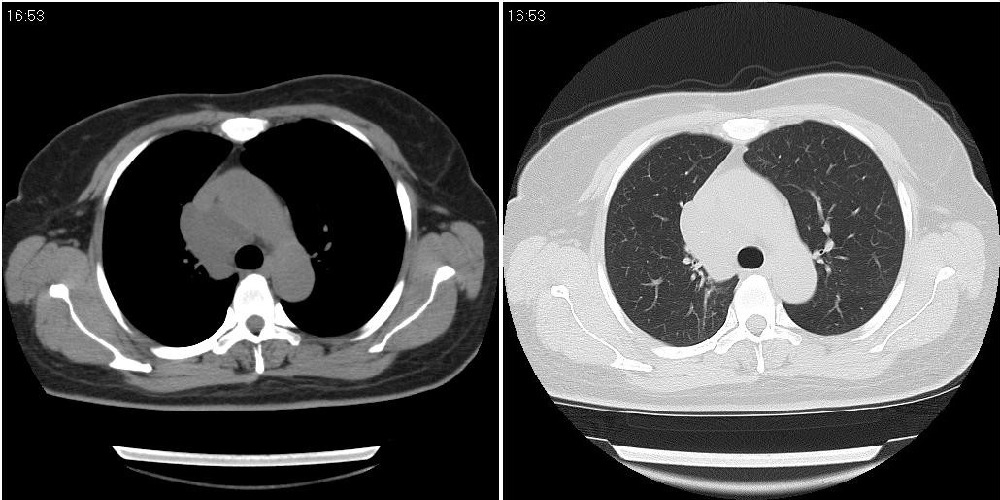

标题: CT24795:女性,47岁,右下腿静脉静脉曲张手术前体检,发现 [打印本页]

标题: CT24795:女性,47岁,右下腿静脉静脉曲张手术前体检,发现

囊性无明显占位效应:1淋巴管囊肿2畸胎瘤(其上部见小钙化)3前肠囊肿

右上纵隔囊性占位性病变;考虑淋巴管囊肿,不排除支气管囊肿。

支气管囊肿、囊性畸胎瘤、肠源性囊肿均有可能。

右上纵隔囊性占位性病变;考虑淋巴管囊肿,不排除支气管囊肿。 建议增强。

考虑淋巴管囊肿,不排除前肠囊肿。